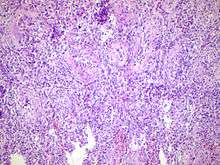

Histopathology image of inflamed epidiymis and testis

Epididymitis can be classified as acute, subacute, and chronic, depending on the duration of symptoms.[4]